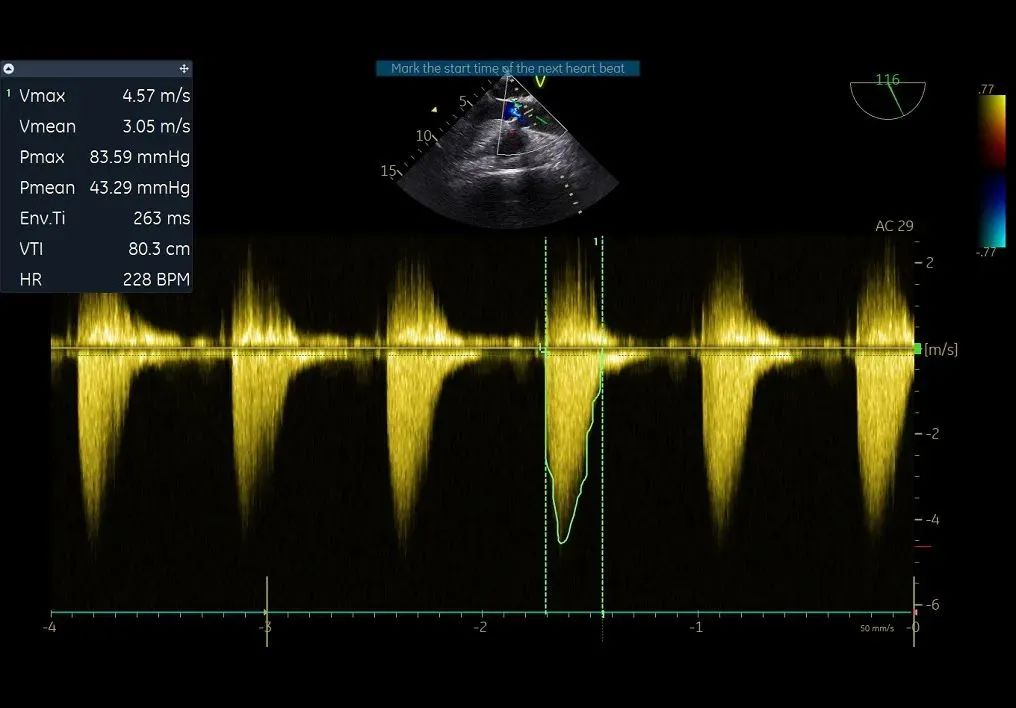

主动脉瓣狭窄(重度),收缩期主动脉瓣上流速增快,最大流速约4.5m/s,最大压差约82mmHg,平均流速约3.3m/s,平均压差约49mmHg。左室肥厚,左室舒张功能减低。D-Dimer5.22mg/1FEU,NT-proBNP780.3pg/ml,hsTNI最高270pg/ml,CK-MB最高4.9ng/ml,肌酐56μmol/L,血钾3.7mmol/L。双下肢大动脉超声显示双侧股动脉多发斑块。双侧锁骨下动脉超声未见明显异常。双侧颈动脉超声显示颈动脉内中膜增厚、斑块形成。双下肢深静脉超声显示双下肢深静脉未见血栓。主动脉+腹主动脉+髂动脉CTA:主动脉、髂动脉粥样硬化,主动脉瓣钙化。冠脉造影显示RCA中重度狭窄,于RCA植入支架2枚。